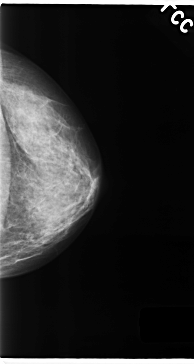

Digital Database for Screening Mammography

Volume: cancer_05 Case: C-0154-1

C_0154_1.RIGHT_CC

LEFT_CC LINES 4728 PIXELS_PER_LINE 2512 BITS_PER_PIXEL 12 RESOLUTION 50 NON_OVERLAY